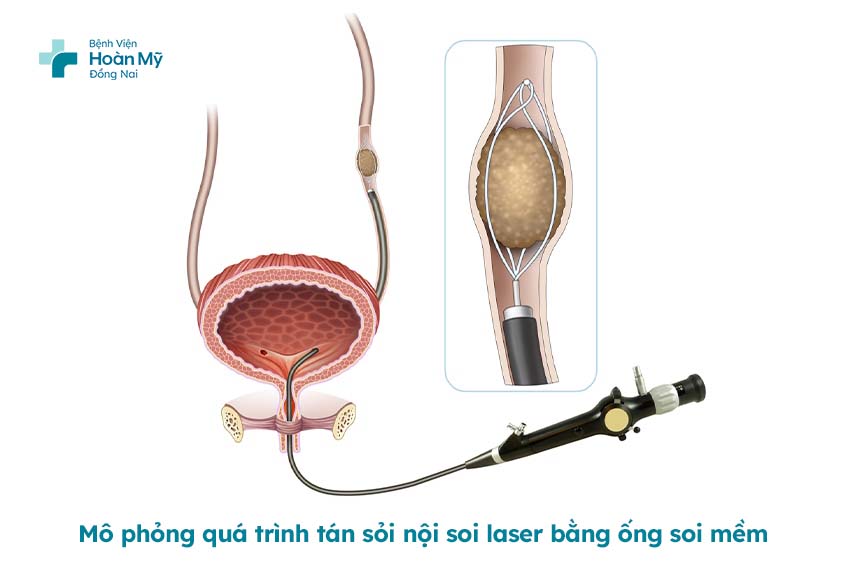

Tán sỏi thận nội soi ngược dòng bằng laser dùng ống mềm là phương pháp tán sỏi qua đường tự nhiên không có tác động của dao kéo vào cơ thể.

Với phương pháp này một ống nội soi mềm được đưa từ lỗ tiểu vào niệu đạo, đến niệu quản và lên thận tìm vị trí của sỏi. Sau đó, dùng năng lượng laser để phá sỏi thành những vụn nhỏ và đưa chúng ra bên ngoài qua quá trình tự đào thải sỏi.

Trong quá trình phẫu thuật, bệnh nhân được gây mê và nằm theo tư thế sản khoa. Bác sĩ sẽ đưa ống nội soi mềm vào niệu quản và sử dụng sóng laser để tán sỏi thành từng mảnh nhỏ.

Các mảnh sỏi sau đó được bơm rửa và lấy ra ngoài bằng rọ. Khi sỏi đã được loại bỏ hoàn toàn, bác sĩ sẽ rút ống nội soi mềm, đặt thông niệu quản ngược dòng và hoàn tất quá trình phẫu thuật.

Mô phỏng chi tiết quá trình tán sỏi nội soi laser bằng ống soi mềm tại Bệnh viện Hoàn Mỹ Đồng Nai